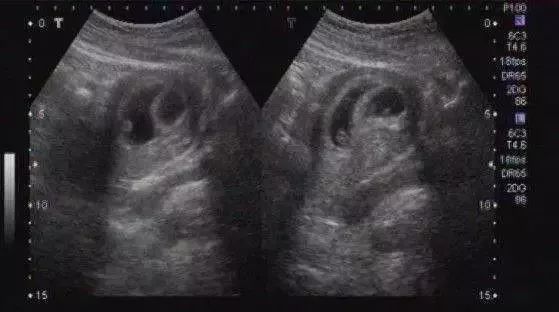

孕期,不管是腹壁B超还是经阴道B超,都是无法做到三维重建,只能根据超声检测到的2-3个径线来描述孕囊的大小。大家拿到手的B超报告,数值接近的,容易被理解为是圆形,有的数值差距太大,就被理解为椭圆形。

B超能看到性别,得等到长出外生殖器

超声看到的是形态上的影像,当胎儿的外生殖器长到可以通过超声看到的程度,就可以进行检查了。一般需要怀孕3-4月以后了,不过误差也比较大。更何况,我们国家法律明令禁止孕期看性别,所以,你就别想拉。